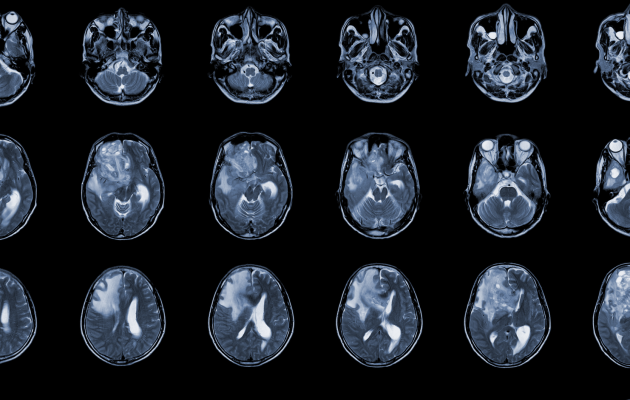

Beyin ödemi tanısı için kullanılan yöntemler, ödemin varlığını, yerini ve büyüklüğünü belirlemek amacıyla çeşitli görüntüleme tekniklerini içerir. En yaygın kullanılan yöntemler arasında bilgisayarlı tomografi (Beyin BT) taramaları ve manyetik rezonans görüntüleme (MR) bulunur. BT taramaları, beyindeki anormallikleri hızlı bir şekilde tespit edebilir ve özellikle acil durumlar için tercih edilen bir yöntemdir. Beyin MR, beyin dokusunun daha detaylı görüntülerini sağlar ve ödemin türünü (vazojenik veya sitotoksik) ayırt etmede BT’ye göre daha duyarlı olabilir.